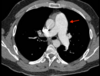

A

Consolidación alveolar